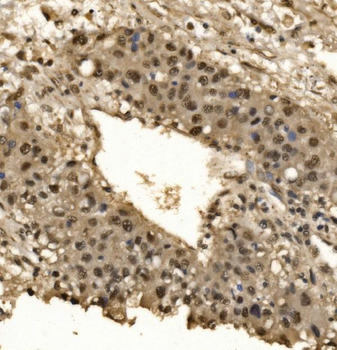

100 μl, 50 μl, 200 μl - ATF4 Recombinant Rabbit Monoclonal Antibody [orb704304]Featured

FC, ICC, IF, IHC-Fr, IHC-P, WB

Human

Mouse

Rabbit

Recombinant

Unconjugated

50 μl, 100 μl - MARK3 Recombinant Rabbit Monoclonal Antibody [orb704310]Featured